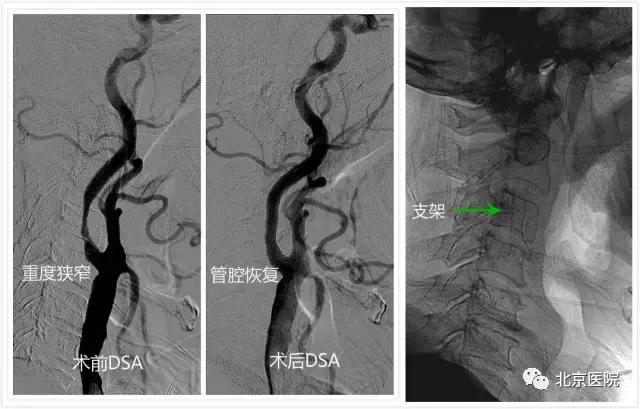

日前,一位88岁老人家属发来的短信让北京医院神经外科的全体医护人员倍感欣喜。原来,这位老人在春节前因“突发左侧肢体瘫痪”在我院确诊为“急性脑梗死”和“颈动脉重度狭窄”,家人告诉医生,老人几年前就因“记性不好、整天瞌睡”在其他医院诊断了“老年痴呆”,现在已“生活自理困难”。在完善相关准备后,我院神经外科为其实施了“微创”的颈动脉狭窄支架成形术。术后老人一改之前的“萎靡不振”,竟然“兴致勃勃”地与旁人聊起了家常,第二天就要求出院回家过春节去……这不,春暖花开,老人特意嘱托家属发来短信,感谢北京医院神经外科医护人员帮他度过了一个健康快乐的春节。

需要关注的是,颈动脉狭窄的患者不仅可以表现为黑朦、言语不清和肢体偏瘫等急性脑中风症状,还可以表现为前面那位老人一样不太典型的“头昏”、“记忆力降落”、“认知功能障碍”等“慢性脑缺血”症状,以往很容易被当成“老年痴呆”。

针对颈动脉狭窄,早在上世纪90年代,北京医院神经外科刘树山主任就开展了颈动脉内膜剥脱术;2002年,在国内最早报道了采用脑保护装置辅助进行颈动脉狭窄支架成形术。神经外科还与神经内科、放射科、超声医学科、核医学科等兄弟科室开展长期合作,围绕颈动脉狭窄患者的认知功能、脑血流灌注、颈动脉斑块稳定性等热点和难点问题,进行了深入的临床和基础研究;先后承担了原国家卫生部临床学科重点项目、首发基金项目、北京医院“121项目”等多项科研课题;发表相关学术论文30余篇;主办了大型脑血管病研讨会10余次。值得一提的是,作为国家老年医学中心,北京医院接诊的颈动脉狭窄患者一直以老年、高龄患者居多,仅在2016年,就治疗了老年颈动脉狭窄患者74例(占总数70%多),无一例出现严重手术并发症。